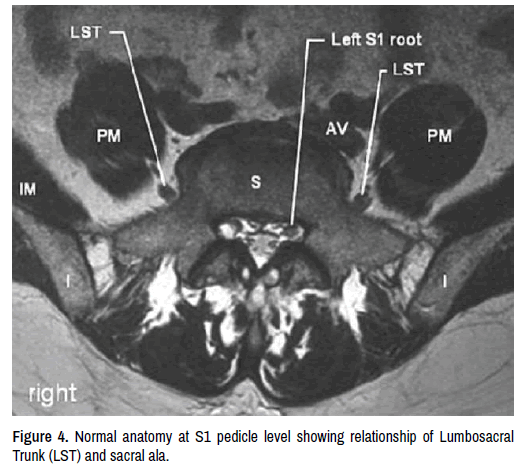

spine-lumbosacral-trunk

Figure 4. Normal anatomy at S1 pedicle level showing relationship of Lumbosacral Trunk (LST) and sacral ala.

Lumbosacral fusion is the standard treatment in case of lumbosacral instability or deformities. Stable internal fixation of the lumbosacral junction along with the grafting is needed to obtain a high rate of solid fusion [4]. Sacral pedicle screws with a good bony purchase will increase the stability and fusion rates. It has been well described that S1 pedicle screw can have anteromedial and anterolateral trajectories either 30° medial into the pedicle or 45° to 50° lateral into the sacral ala with a 10° to 20°caudal tilt in the sagittal plane [5]. Cadaveric studies done previously regarding sacral pedicle screw placement describes the risk of injury to lumbosacral trunk (L4-L5) [6]. The L4 nerve root joins the L5 nerve root superior to the first sacral foramen. In 33% cases L4 nerve roots may join the L5 nerve root lower down above the most anterior part of the sacroiliac joint thereby increasing the chance of direct L4 nerve root injury also [7]. The L5 nerve root is the closest anterior relation to the sacrum running just 0.1 mm off of the anterior periosteal surface [8]. L5 nerve root location can also be variable with its position occurring either laterally on the ala near the SI joint or medially over the Sacral pedicle. Even though previous studies by Krag et al. and Roy-Camille et al. strongly recommended avoiding anterior cortex penetration as it increases the risk of neurovascular injury, the increased biomechanical stability and pull out strength of bicortical screw have been well documented in the literature [9-11]. To increase, the stability many spine surgeons opt for a bicortical sacral screw. Cadaveric study by Ergur et al. also described risk of neurovascular injury with anterior cortical penetration [12].